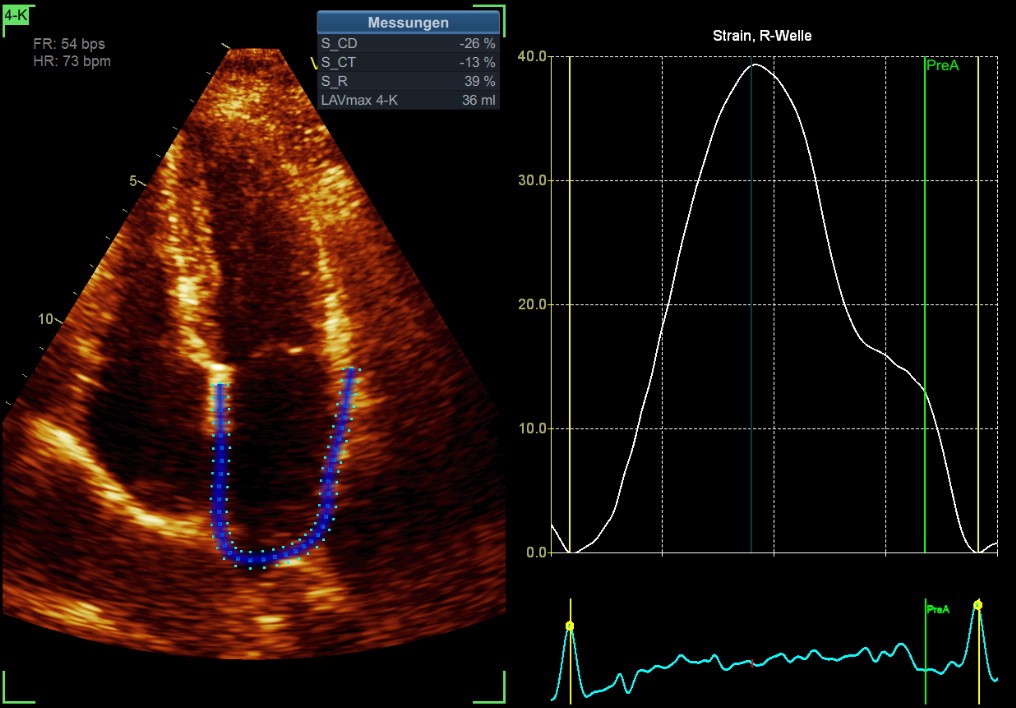

20-39a ➜ LASr 47%

40-59a ➜ LASr 41%

>60a ➜ LASr 36%

LASr: Left atrial stain reservoir

(normal value around 39%)

LASct: Left atrial strain contraction

(normal value around -17%)

Normal LA Strain

LA-Strain in the 4-ChV & 2-ChV

Optimally always 4-ChV & 2-ChV

Clinically easier & often sufficient is the LA Strain of the 4-ChV

R to R > P-wave to P-wave (easier to see and to measure) in the EKG

PALS = LASr

PACS = LASct

Conduit = LAScd